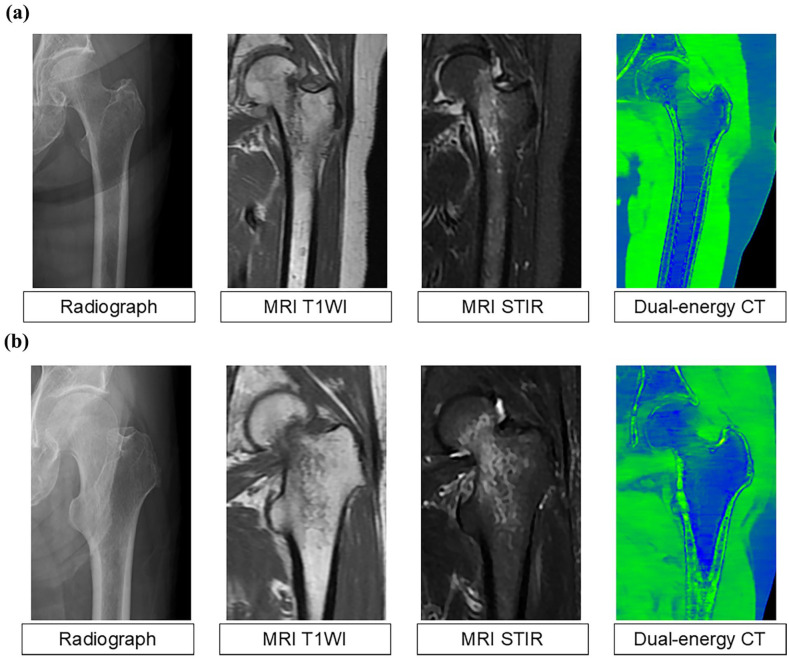

Objectives: Early surgical intervention within 48 h is critical for reducing mortality and morbidity in patients with hip fractures. However, occult hip fractures are often missed, leading to treatment delays. Dual-energy computed tomography allows visualization of bone marrow edema and bone contusions, which are challenging to detect using conventional computed tomography. This study aimed to evaluate the effectiveness of dual-energy computed tomography in diagnosing occult hip fractures.

Methods: Eighteen dual-energy computed tomography scans obtained between May 2018 and March 2024 were analyzed. Magnetic resonance imaging was performed in all cases. A trained musculoskeletal radiologist interpreted the dual-energy computed tomography and magnetic resonance imaging scans, which were then reviewed by two senior orthopedic surgeons. The confirmed diagnoses included 14 femoral trochanteric fractures and 4 femoral neck fractures. Four junior orthopedic surgeons independently reviewed the dual-energy computed tomography scans only and conducted diagnostic examinations. Patients were subsequently categorized into two groups: those with unanimous diagnostic agreement (unanimity group) and those with discrepancies (objection group).

Results: For femoral trochanteric fractures, sensitivity, specificity, accuracy, and Cohen's kappa coefficient were 94%, 81%, 0.91, and 0.75, respectively. For femoral neck fractures, sensitivity, specificity, accuracy, and Cohen's kappa coefficient were 68%, 96%, 0.90, and 0.69, respectively. A significant difference in diagnostic ease was noted (p = 0.04), with agreement achieved for 12 of the 14 femoral trochanteric fractures and one of the four femoral neck fractures. Logistic regression analysis yielded a regression coefficient for femoral trochanteric fractures of 3.05 (p = 0.03), indicating that these fractures were more easily diagnosed than femoral neck fractures.

Conclusions: Dual-energy computed tomography demonstrated high sensitivity and specificity in detecting occult hip fractures, particularly those of the femoral trochanter. However, its sensitivity was lower for femoral neck fractures, indicating limited reliability in their diagnosis. Further investigation and magnetic resonance imaging scans are recommended for suspected femoral neck fractures.